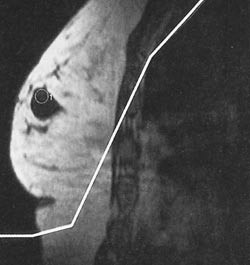

Over 1 900 nederlandske kvinner med høy risiko for brystkreft, dvs. med brystkreftrelaterte mutasjoner (n = 358) eller familieanamnese på brystkreft, gjennomgikk klinisk undersøkelse, MR og mammogafi hver 6. måned (1). Etter 2,9 år (median) ble 51 tumorer og ett lobulært carcinoma in situ påvist. Sensitivitet for mammografi og MR var henholdsvis 33 og 80 %, spesifisitet 95 og 90 %. Andelen invasive tumorer med diameter ≤10 mm var langt større (43 %) enn i to aldersjusterte kontrollgrupper.

– Denne ikke-randomiserte studien viser at ved et screeningprogram med MR kan brystkreft påvises i en tidlig fase hos kvinner med særlig høy risiko for brystkreft, sier seksjonsoverlege Ellen Schlichting ved Ullevål universitetssykehus. MR hadde høyere sensitivitet, men lavere spesifisitet enn mammografi, noe som medfører flere tilleggsundersøkelser ved suspekte funn. For kvinner med særlig høy risiko for brystkreft, spesielt dem med BCRA-mutasjon, har dette likevel mindre betydning.